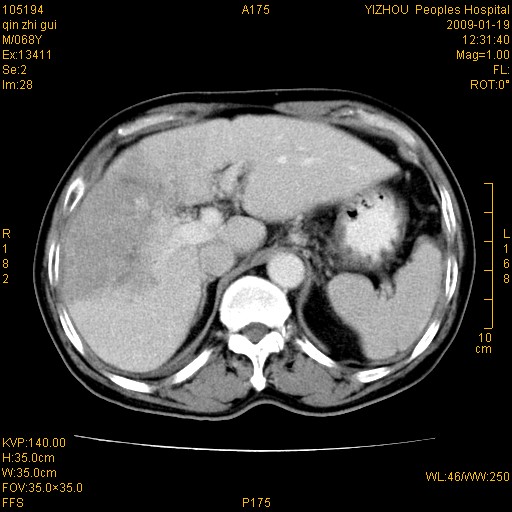

以下是引用随光逐影在2009-1-21 16:11:00的发言:[br]1)考虑肝右叶肝癌并肝静脉及门静脉瘤栓形成。2)肝硬化,少量腹水。3)胆囊炎。4)右侧少量胸腔积液。

病灶外缘凹凸不平,平扫低密度,增强动脉期有强化,门脉早显,静脉期及延期呈延迟强化,结合病史考虑右肝前叶巨块型肝癌可能性大,强化表现不除外胆管细胞癌